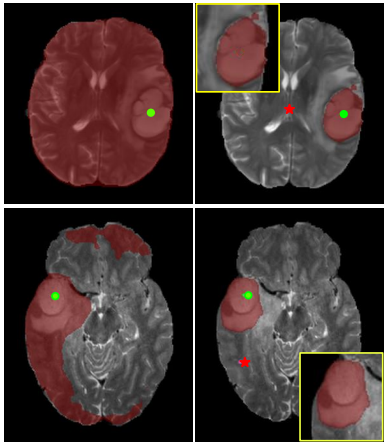

Few-Shot 3D Volumetric Segmentation with Multi-Surrogate Fusion

We present MSFSeg, a novel few-shot 3D segmentation framework with a lightweight multi-surrogate fusion (MSF). MSFSeg is able to automatically segment unseen 3D objects/organs (during training) provided with one or a few annotated 2D slices or 3D sequence segments.

Implicit Modeling of Non-rigid Objects with Cross-Category Signals

In this work, we propose MODIF, a multi-object deep implicit function that jointly learns the deformation fields and instance-specific latent codes for multiple objects at once. Our emphasis is on non-rigid, non-interpenetrating entities such as organs.